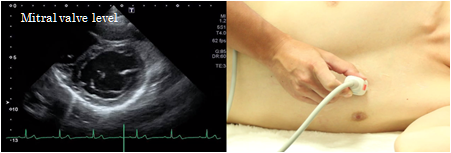

Mitral orifice level

The mitral orifice level of the short axis view of the left ventricle depicts the mitral valve with a large anterior cusp in the front and a small and wide posterior cusp at the backside of the image. The anterior commissure is located on the right side of the screen and the posterior commissure on the left side. This view is used to determine the site of mitral valve prolapse and measure the mitral valve area in case of mitral valve stenosis.